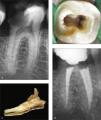

Carlsen y Alexandersen32 reseñaron el estudio de 398 molares inferiores permanentes con un complejo radicular y una raíz supernumeraria localizada lingualmente. Esta macroestructura, denominada radix entomolaris, presenta una elevada variación respecto al plano mesiodistal coronal. Cuando la posición de esta tercera raíz es vestibular, se denomina radix paramolaris. Solo dos publicaciones han descrito la presencia de una raíz adicional vestibular al principal conducto distal33,34. Su forma y curvatura son muy variables27,35,36 y puede variar desde la presentación de una corta extensión cónica hasta la presencia de una raíz completamente normal (fig. 2a–c). Lo más típico es que el eje de la raíz se enfrente a la cara vestibular del molar. Por ello, a la hora de medir la longitud del conducto radicular resulta más fácil seleccionar como punto de referencia la cúspide distovestibular que la cúspide distolingual que habitualmente se emplea (fig. 2d). La inclinación del orificio junto con la curvatura vestibular del tercio apical (fig. 4c) resultan en un conducto muy complejo de instrumentar e irrigar. Para evitar percances, cuando se trata la porción apical, es aconsejable escoger instrumentos pequeños y muy flexibles. La figura 4 muestra un primer molar inferior con tres raíces extraído como consecuencia de un fracaso endodóncico producido por perforación por desgaste (stripping) de la raíz distolingual (fig. 4d).

Primer molar inferior con tres raíces extraído como consecuencia de un fracaso endodóncico debido a perforación por desgaste (stripping de la raíz distolingual. (a) Imagen oclusal con la extensión de la apertura de acceso hacia la raíz distolingual. (b) Imagen desde la cara distal; se observa la curvatura vestibular de la raíz distolingual. (c) Imagen vestibular que demuestra la localización y ángulo apical de la raíz distolingual. (d) Imagen clara de una perforación por desgaste (flecha) en el interior de la raíz distolingual.

En un 0,8% de las muestras se encontraron cinco conductos, e incluso algunas reseñas de casos han llegado a referir seis42 e incluso siete conductos radiculares43. En la figura 4 se ilustra la compleja anatomía de un primer molar inferior que presentaba seis conductos radiculares con tres conductos mesiales separados. Se observa que en el conducto distovestibular se retiró material de obturación para crear espacio para un poste.